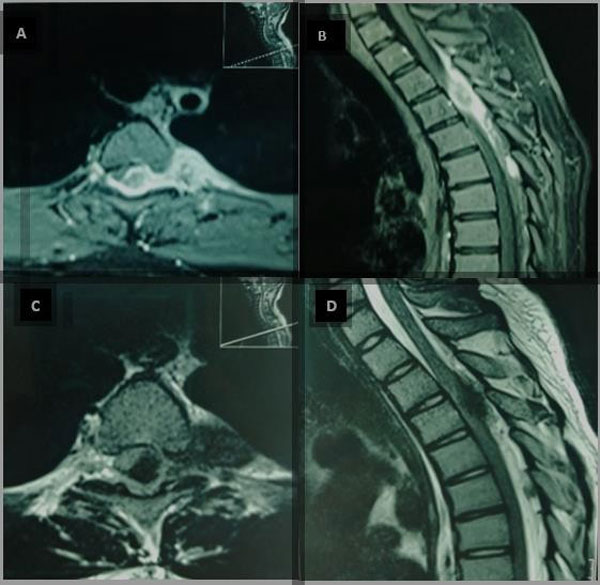

Durante su internación se realizaron estudios por imágenes. En la resonancia se evidenció tumor dorsal (D2-D5) de probable origen neurogénico localizado a nivel epidural que se extendía a la región paravertebral izquierda (Figura 1). En los estudios de laboratorio se encontró incremento de la velocidad de sedimentación globular, hemograma compatible con anemia microcítica e hipocrómica, ligera leucocitosis con neutrofilia. Marcadores tumorales, examen serológico y perfil autoinmune dentro de parámetros normales.

Figura 1. RM de columna dorsal. A y B) Con contraste. Evidencia lesión hipercaptadora homogénea que se extiende desde D2 – D6 con efecto de compresión medular extradural, principalmente a nivel de D3, con extensión a región paravertebral izquierda. C y D) En T2 se evidencia lesión hipointensa con efecto de compresión sobre médula espinal con extensión paravertebral izquierda hasta pleura parietal torácica.

Los estudios por resonancia magnética (RM) pueden mostrar patrones heterogéneos, iso o hipointensos en secuencias T1 y T2, que mejoran con la captación de contraste. Xu y col.(2) describen lesión isointensa de la médula espinal en T1 y heterogéneamente hipointensa en secuencia T2, con buena captación de contraste. Elsotouhy y col.(10) describen una masa de tejido blando con base dural, tanto epidural como subdural extramedular, que causan compresión de la médula espinal iso e hipointensas en secuencias T1 y T2 que se vuelven homogéneas con la administración de contraste.